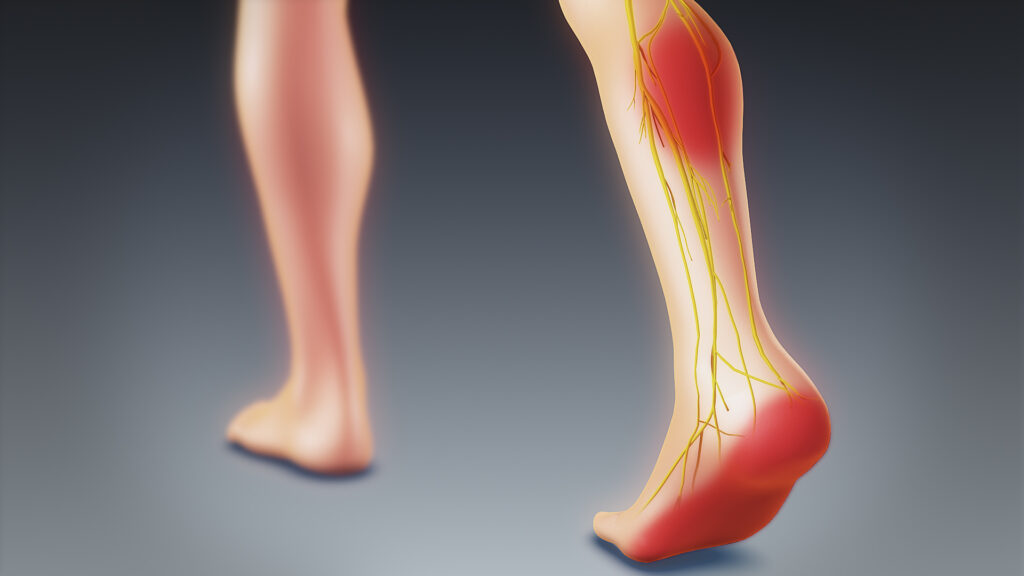

علائم پا درد عصبی

علائم پا درد عصبی پا درد یکی از شایعترین مشکلاتی است که میلیونها نفر در سراسر جهان تجربه میکنند. با این حال همه پا دردها منشأ یکسانی...

درمان عصب سیاتیک پای چپ

درمان عصب سیاتیک پای چپ درد سیاتیک یکی از شایعترین درمان درد عصبی در جهان است که بسیاری از افراد آن را تجربه میکنند. این درد زمانی ای...

درمان زود عصب سیاتیک پای راست

درمان زود عصب سیاتیک پای راست یکی از شایعترین دلایل کمردرد و دردهای تیرکشنده پا است که میلیونها نفر در سراسر جهان را درگیر میکند. ای...